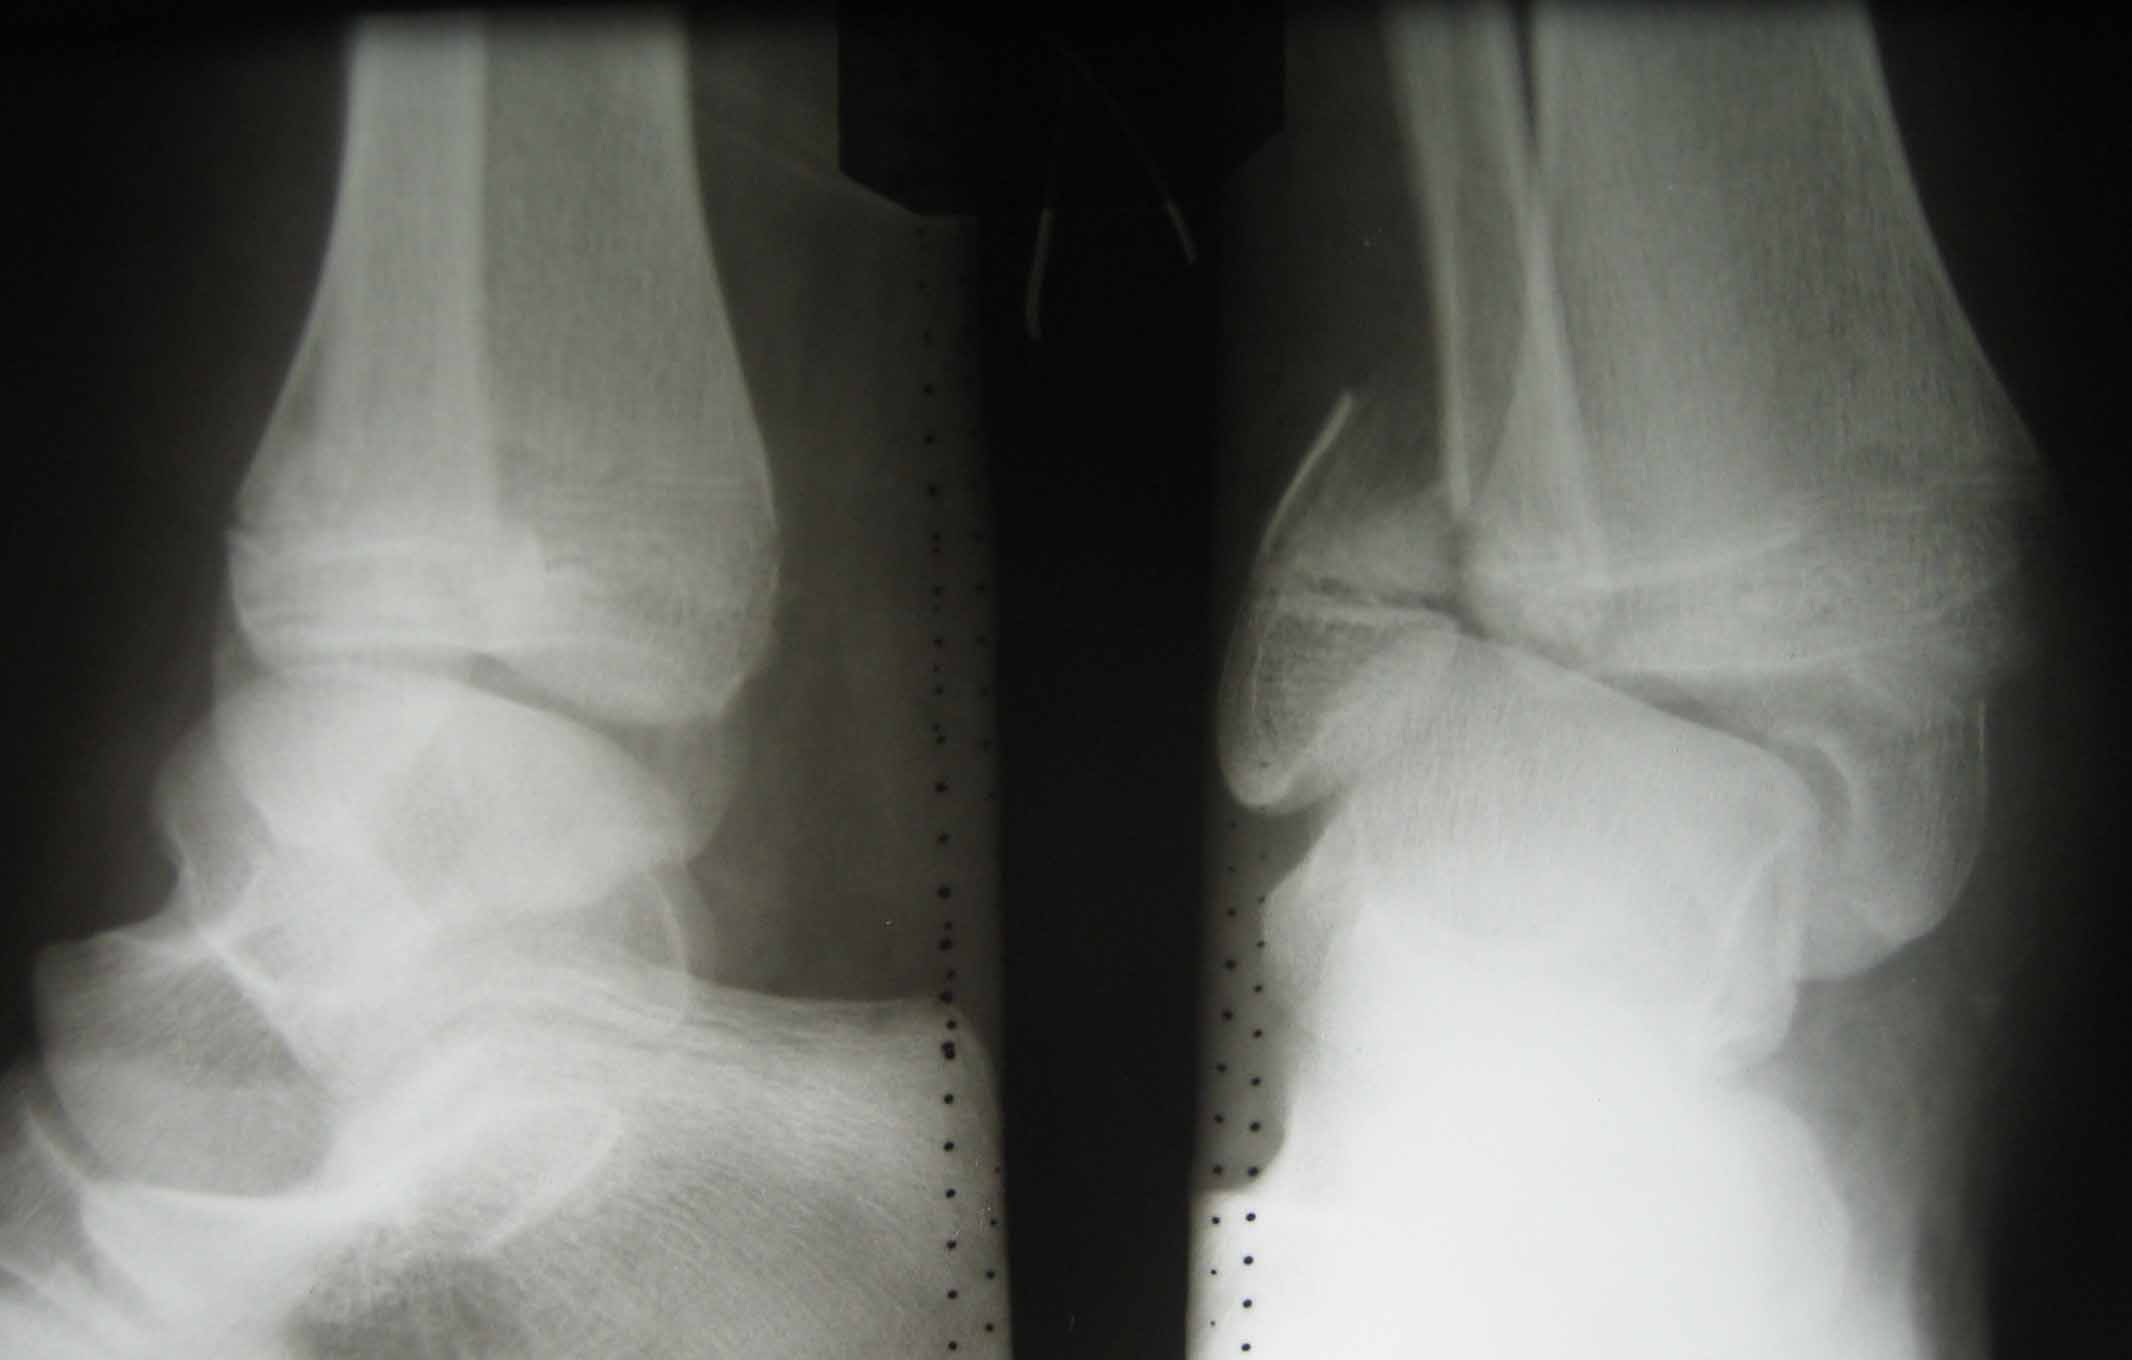

В июле 2009 года - перелом лодыжек. Лечили в гипсе, потом в аппарате.

Лечили спорно, на мой взгляд. В результате - - сращение наружной

лодыжки с укорочением, подвывих голеностопа кнаружи (вальгус) в итоге

компенсаторно передний отдел стопы ставит на варус. Нагрузку

ограничивает.

Снимки в приложении.

Имя     : июль 2009.jpg

Тип     : image/jpeg

Размер  : 87868 байтов

Описание: отсутствует

Url     : http://weborto.net:8080/pipermail/ortho/attachments/20100123/d8a7ad29/attachment-0003.jpg